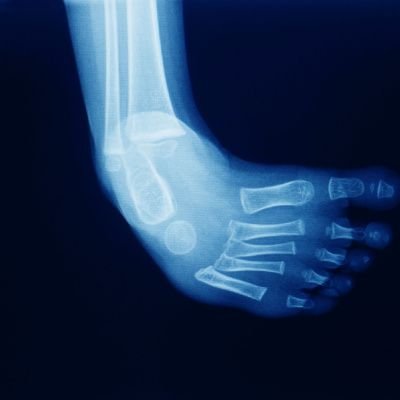

Imaging Studies

X-rays or ultrasounds may be recommended to visualize the bones and joints of the foot, providing additional insights into the severity and specific aspects of the clubfoot.